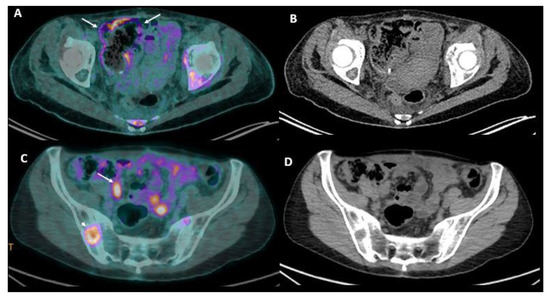

2.3. Positron Emission Tomography (PET)-CT

2.4. Imaging Combination

6.1. PET/MR

6.2. Novel PET Radiotracers